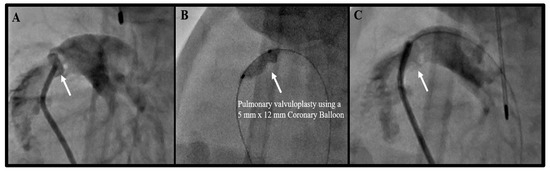

| 2. Pulmonary Valvuloplasty | 9 |

| 2. Pulmonary Valvuloplasty *∂€ | 9 | 0 | 0 | 6 |

| 7. Pulmonary valve perforation for pulmonary atresia | 2 |

| 6. Ductal Stent ∂† | 2 | 0 | 0 | 1 |

| 7. Pulmonary valve perforation for pulmonary atresia €∂ | 2 | 0 | 0 | 1 |